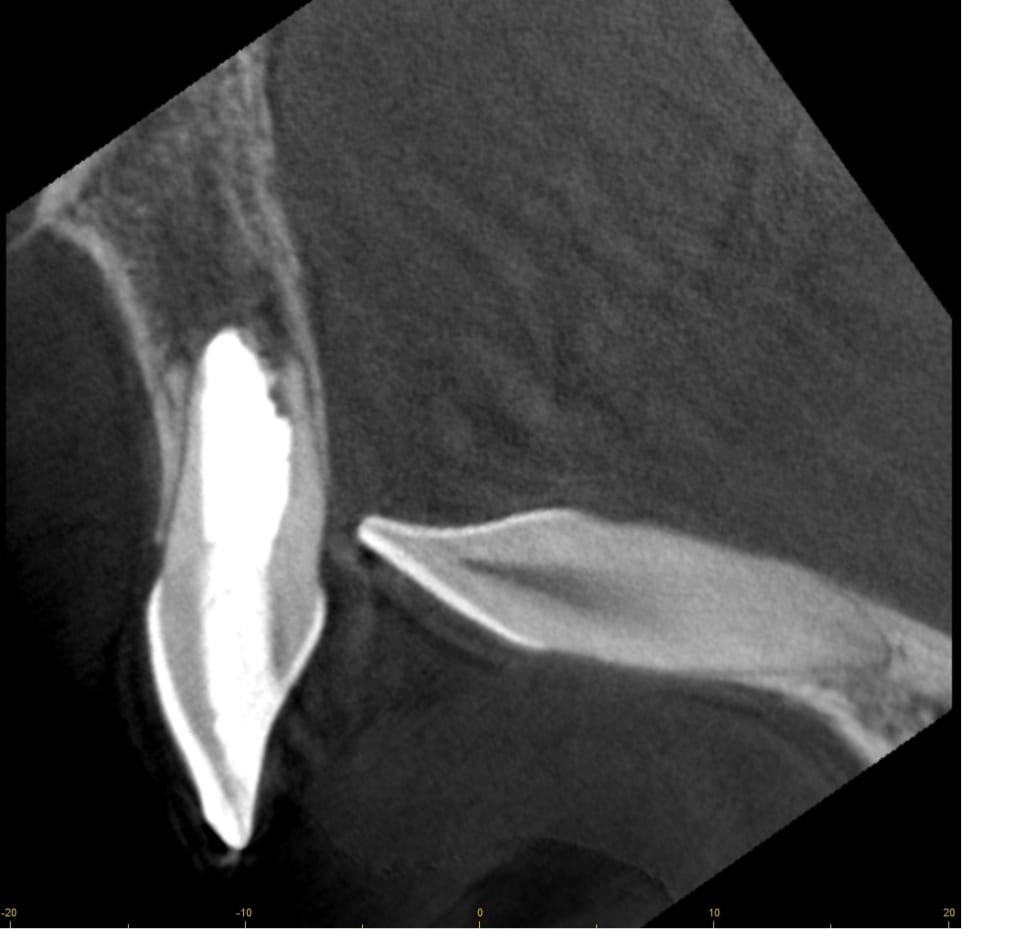

Bal oldalon egy hagyományos gyökérkezelés eredménye látható, míg jobbra ugyanazon fog mikroszkópos módszerrel végzett helyreállítása

Mikroszkóppal akár 20-szoros nagyításban a rejtett, szűk, csatornák pontos feltárása, betört tűk, régi gyökértömés eltávolítása is lehetséges. A mikroszkópos gyökérkezelés olyan esetekben is megoldást jelenthet, amelyeket korábban húzásra ítéltünk volna.

Épp ezért a konzultáció során rendkívül alapos CT elemzést végzünk, majd olyan átgondolt, minden részletre kidolgozott kezelési tervet készítünk, melyben igyekszünk minden lehetőséget számításba venni.